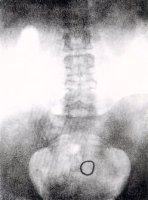

Da esq. para dir. : topo: dispositivo para inserir no anel -Gräfenberg, 3 amostras de anéis, raio-X mostrando a posição onde fica inserido o anel